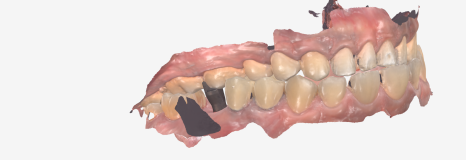

이제 마지막으로 본을 뜨는 과정이 남았는데요~

저희는 고무로 무는 방식이 아닌,

컴퓨터로 정밀하게 본을 뜨는 방식인

구강스캐너를 사용합니다.

무엇보다 디지털 데이터를 통해

제작하기 때문에 더욱 정교한 보철이

제작되는 건 당연한 결과겠죠?